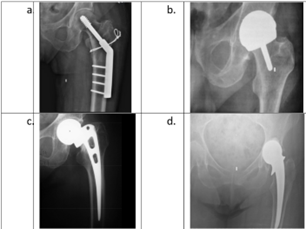

1. Match the following:

1. 1-a, 2-c, 3-b, 4-d

2. 1-c, 2-a, 3-d, 4-b

3. 1-b, 2-d, 3-c, 4-a

4. 1-d, 2-b, 3-a, 4-c